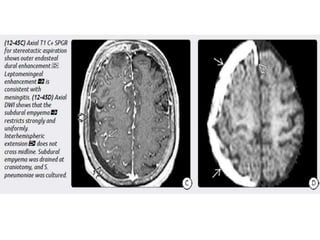

Empyemas

Extraaxial infections of the CNS are rare but potentially life threatening

conditions.

Empyemas are pus collections that can occur in either the subdural or

epidural space.

Empyemas in infants and young children are most commonly

secondary to bacterial meningitis.

In older children and adults, over two-thirds of empyemas occur as

extension of infection from paranasal sinus disease.

Approximately 20% of empyemas in older children and adultsare

secondary to otomastoiditis.

Subdural empyemas (SDEs) are much more common than epidural

empyemas (EDEs).

Imaging

NECT scans may be normal or show a hypodense extraaxial collection

that demonstrates peripheral enhancement on CECT.

Bone CT should be evaluated for signs of sinusitis and otomastoiditis.

MR is the procedure of choice for evaluating potential empyemas. T1

scans show an extraaxial collection that is mildly hyperintense relative to

CSF.

SDEs are typically crescentic and lie over the cerebral hemisphere. SDEs

often extend into the interhemispheric fissure but do not cross the midline.

EDEs are biconvex and usually more focal than SDEs. EDEs may cross

the midline, confirming their epidural location

Empyemas Extraaxial infections ofthe CNS are rare but potentially life threatening conditions. Empyemas are pus collections that can occur in either the subdural or epidural space. Empyemas in infants and young children are most commonly secondary to bacterial meningitis. In older children and adults, over two-thirds of empyemas occur as extension of infection from paranasal sinus disease. Approximately 20% of empyemas in older children and adultsare secondary to otomastoiditis.

• 53.

Subdural empyemas (SDEs)are much more common than epidural empyemas (EDEs). Imaging NECT scans may be normal or show a hypodense extraaxial collection that demonstrates peripheral enhancement on CECT. Bone CT should be evaluated for signs of sinusitis and otomastoiditis. MR is the procedure of choice for evaluating potential empyemas. T1 scans show an extraaxial collection that is mildly hyperintense relative to CSF. SDEs are typically crescentic and lie over the cerebral hemisphere. SDEs often extend into the interhemispheric fissure but do not cross the midline. EDEs are biconvex and usually more focal than SDEs. EDEs may cross the midline, confirming their epidural location